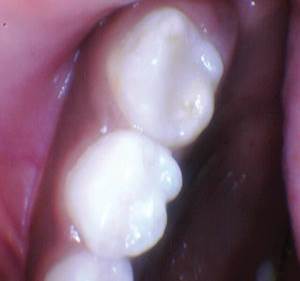

Figura 3. Después del grabado selectivo y el uso de Scotchbond Universal, el diente se restauró con Activa Restorative A2. |

Figura 4. El seguimiento de 18 meses no mostró fracturas y márgenes intactos. |